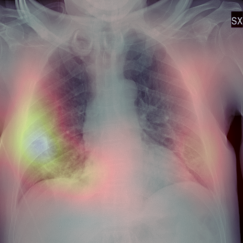

Early screening of patients is a critical issue in order to assess immediate and fast responses against the spread of COVID-19. The use of nasopharyngeal swabs has been considered the most viable approach; however, the result is not immediate or, in the case of fast exams, sufficiently accurate. Using Chest X-Ray (CXR) imaging for early screening potentially provides faster and more accurate response; however, diagnosing COVID from CXRs is hard and we should rely on deep learning support, whose decision process is, on the other hand, "black-boxed" and, for such reason, untrustworthy. We propose an explainable two-step diagnostic approach, where we first detect known pathologies (anomalies) in the lungs, on top of which we diagnose the illness. Our approach achieves promising performance in COVID detection, compatible with expert human radiologists. All of our experiments have been carried out bearing in mind that, especially for clinical applications, explainability plays a major role for building trust in machine learning algorithms.